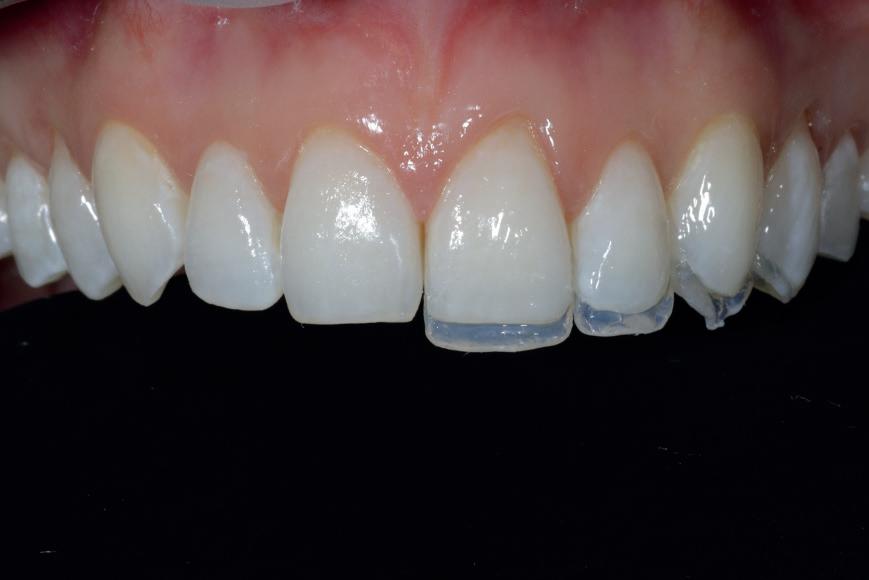

Case 1: Anterior tooth restoration with composite

Case 2: Posterior tooth restoration with composite

Restorations with Beautifil II LS, Beautifil Flow Plus X and OneGloss by Erik-Jan Muts, M.Sc., Netherlands